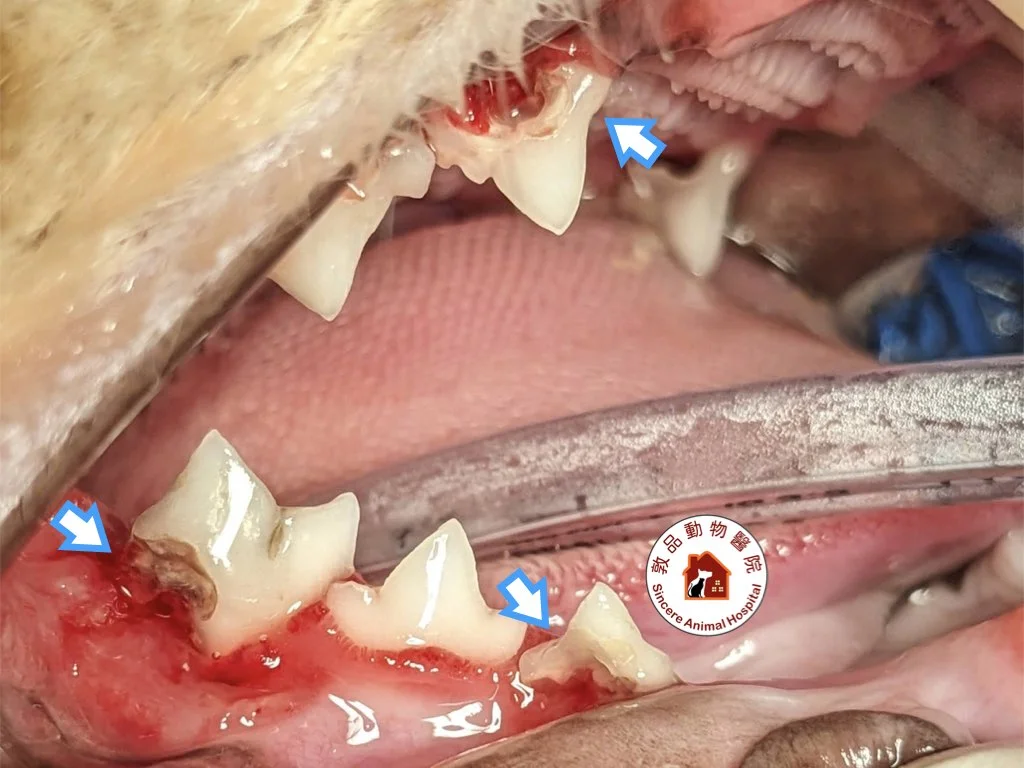

圖片中可以明顯見到上下排牙齒破裂情況

- 牙齦嚴重紅腫或出血

- 可見的牙齒破損

視覺檢查

獸醫會觀察:

- 牙齦紅腫程度

- 牙齒表面破損

- 紅色肉芽組織增生

- 牙齒變色或缺損